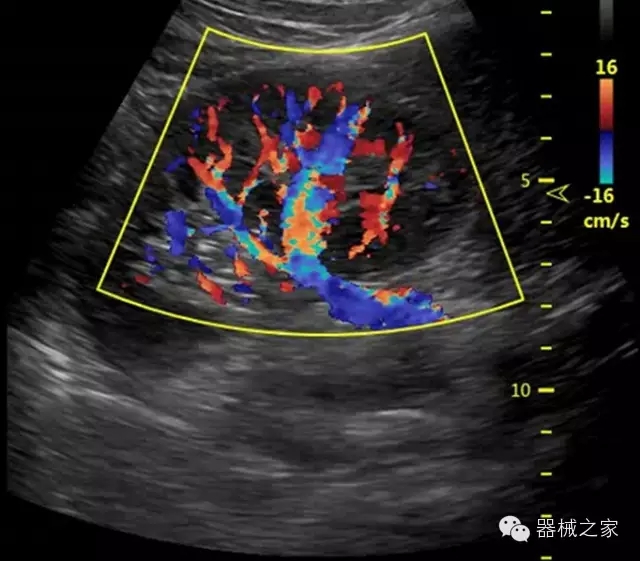

品牌:開立(SONOSCAPE)

深圳開立生物醫(yī)療科技股份有限公司作為中國民族醫(yī)療產(chǎn)業(yè)的優(yōu)秀引導(dǎo)者,自成立伊始,一直致力于臨床醫(yī)療設(shè)備的研發(fā)和制造,產(chǎn)品涵蓋醫(yī)用數(shù)字超聲診斷系統(tǒng)、電子內(nèi)窺鏡系統(tǒng)、全自動(dòng)五分類血液細(xì)胞分析儀以及自主研發(fā)的探頭群。

官方網(wǎng)站:www.sonoscape.com.cn

經(jīng)典產(chǎn)品:S8EXP

臨床圖片賞析

產(chǎn)品特點(diǎn)

全面的臨床解決方案

超聲科常規(guī)領(lǐng)域應(yīng)用

·移植S40高端臺式彩超高端平臺技術(shù),滿足超聲科腹部、淺表、婦產(chǎn)科、心血管、肌骨等應(yīng)用,提供超聲科完美解決方案;

·實(shí)時(shí)的彈性成像技術(shù):提高了小器管(乳腺,甲狀腺、淺表軟組織腫瘤等)疾病鑒別診斷;

·IMT血管內(nèi)中膜自動(dòng)測量:為血管性疾病評估提供了有效的評估手段;

·心功能綜合指數(shù)(TEI指數(shù)):用于左、右心室整體心臟收縮舒張功能評估的測量方法;

·全方位可調(diào)M型:有利于更好的觀察心腔大小及室壁階段性運(yùn)動(dòng)的異常情況;

·組織多普勒成像(TDI):TDI可定量評價(jià)心肌運(yùn)動(dòng),判斷是否有局部病變,還可評價(jià)早期的舒張功能;

·高效3D/4D成像技術(shù):高速的4D幀頻,豐富的3D成像模式,智能斷層切片功能;

POC領(lǐng)域解決方案

·外觀小巧;

·穿刺增強(qiáng)技術(shù):可有效提高進(jìn)針區(qū)圖像分辨率,提高進(jìn)針亮度,全面提高一次性穿刺的成功率;

全面的術(shù)中探頭解決方案

·小凸探頭:開放性手術(shù),實(shí)時(shí)監(jiān)測病灶位置,提高手術(shù)成功率,可應(yīng)用于麻醉科、肝膽外科、腫瘤外科、神經(jīng)外科、泌尿外科等手術(shù);

·L型線陣探頭:高分辨率圖像,清晰顯示病灶位置,提高手術(shù)成功率,可應(yīng)用于麻醉科、胸外科、肝膽外科、腫瘤外科、神經(jīng)外科、泌尿外科等應(yīng)用;

·MPTEE:經(jīng)食道探頭術(shù)中監(jiān)測,可測量心臟前負(fù)荷(左室舒張末期大小、右房大?。?、心排血量、后負(fù)荷、收縮功能、室壁運(yùn)動(dòng)分析、肝靜脈血流(與中心靜脈壓相關(guān))等,術(shù)后還能及時(shí)評估手術(shù)效果評估;

·獨(dú)有的大角度及實(shí)時(shí)溫控技術(shù),能同一切面顯示宮頸及宮體,有效減低了患者的痛苦,及保護(hù)粘膜保證了醫(yī)療安全;

高效的人機(jī)工程學(xué)設(shè)計(jì)

·15‘’高清醫(yī)用顯示器;

·內(nèi)置雙探頭接口;

·可升降臺車,1拖3探頭擴(kuò)展器;

·m-Tuning一鍵優(yōu)化;

CFDA注冊證編號

·粵食藥監(jiān)械(準(zhǔn))字20132230491